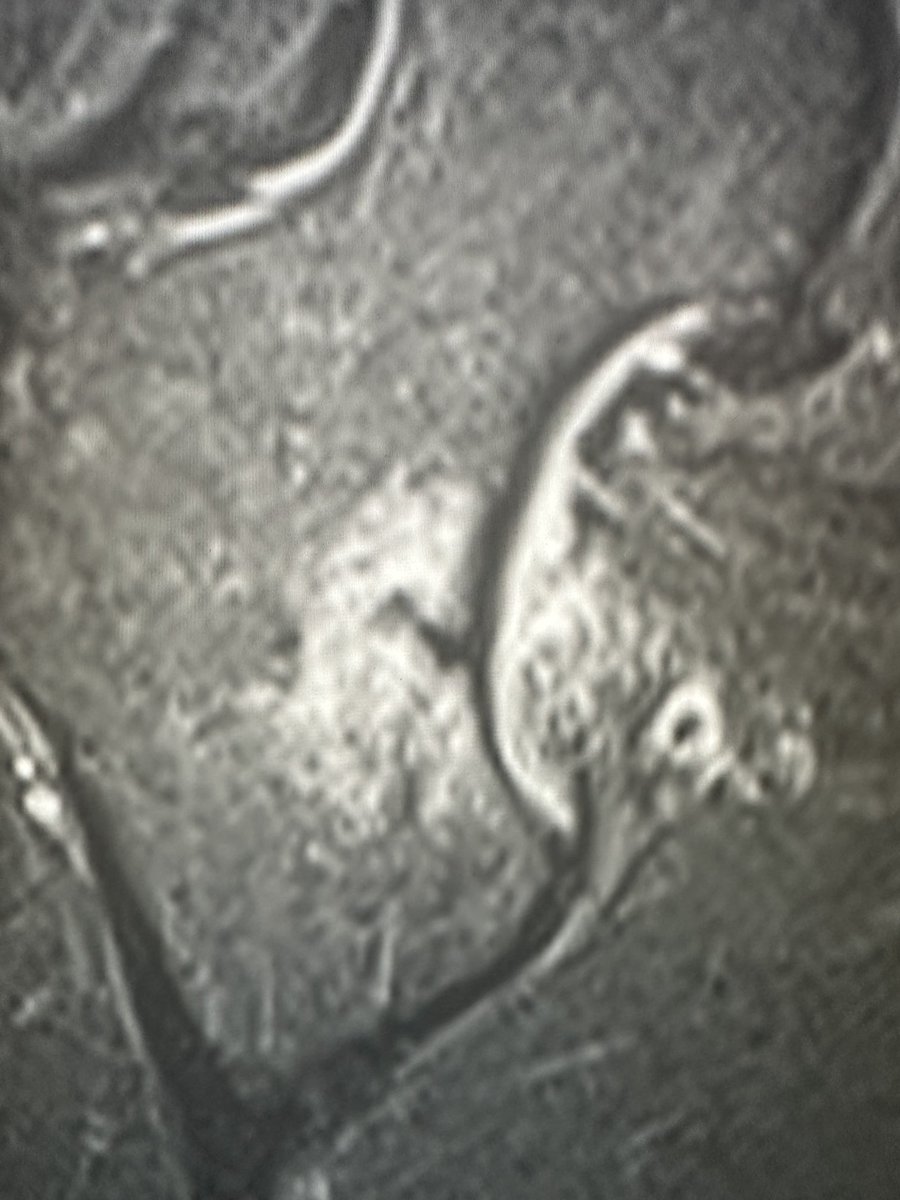

Female 67 y/o - THA

*Approach?

*What stem do you choose?

*Comments & tricks?

@AAHKS_YAG @AAHKS_YAG @JArthroplasty @AAOS1 @CleClinicArthGp